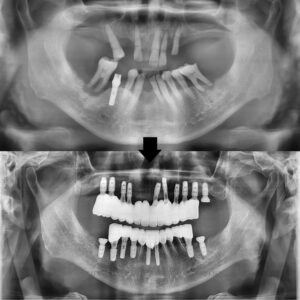

25.02.05 / 25.05.09

치료 전후 사진입니다.

환자분께서는 보이는 앞니 부분이 부러져

보기 싫어 빠르게 치료를 원하셨는데

3개월 만에 끝낼 수 있어서

매우 만족해 주셨습니다.

또한 완성된 보철도

자연스럽고 예쁘다며

좋아해 주셨습니다.